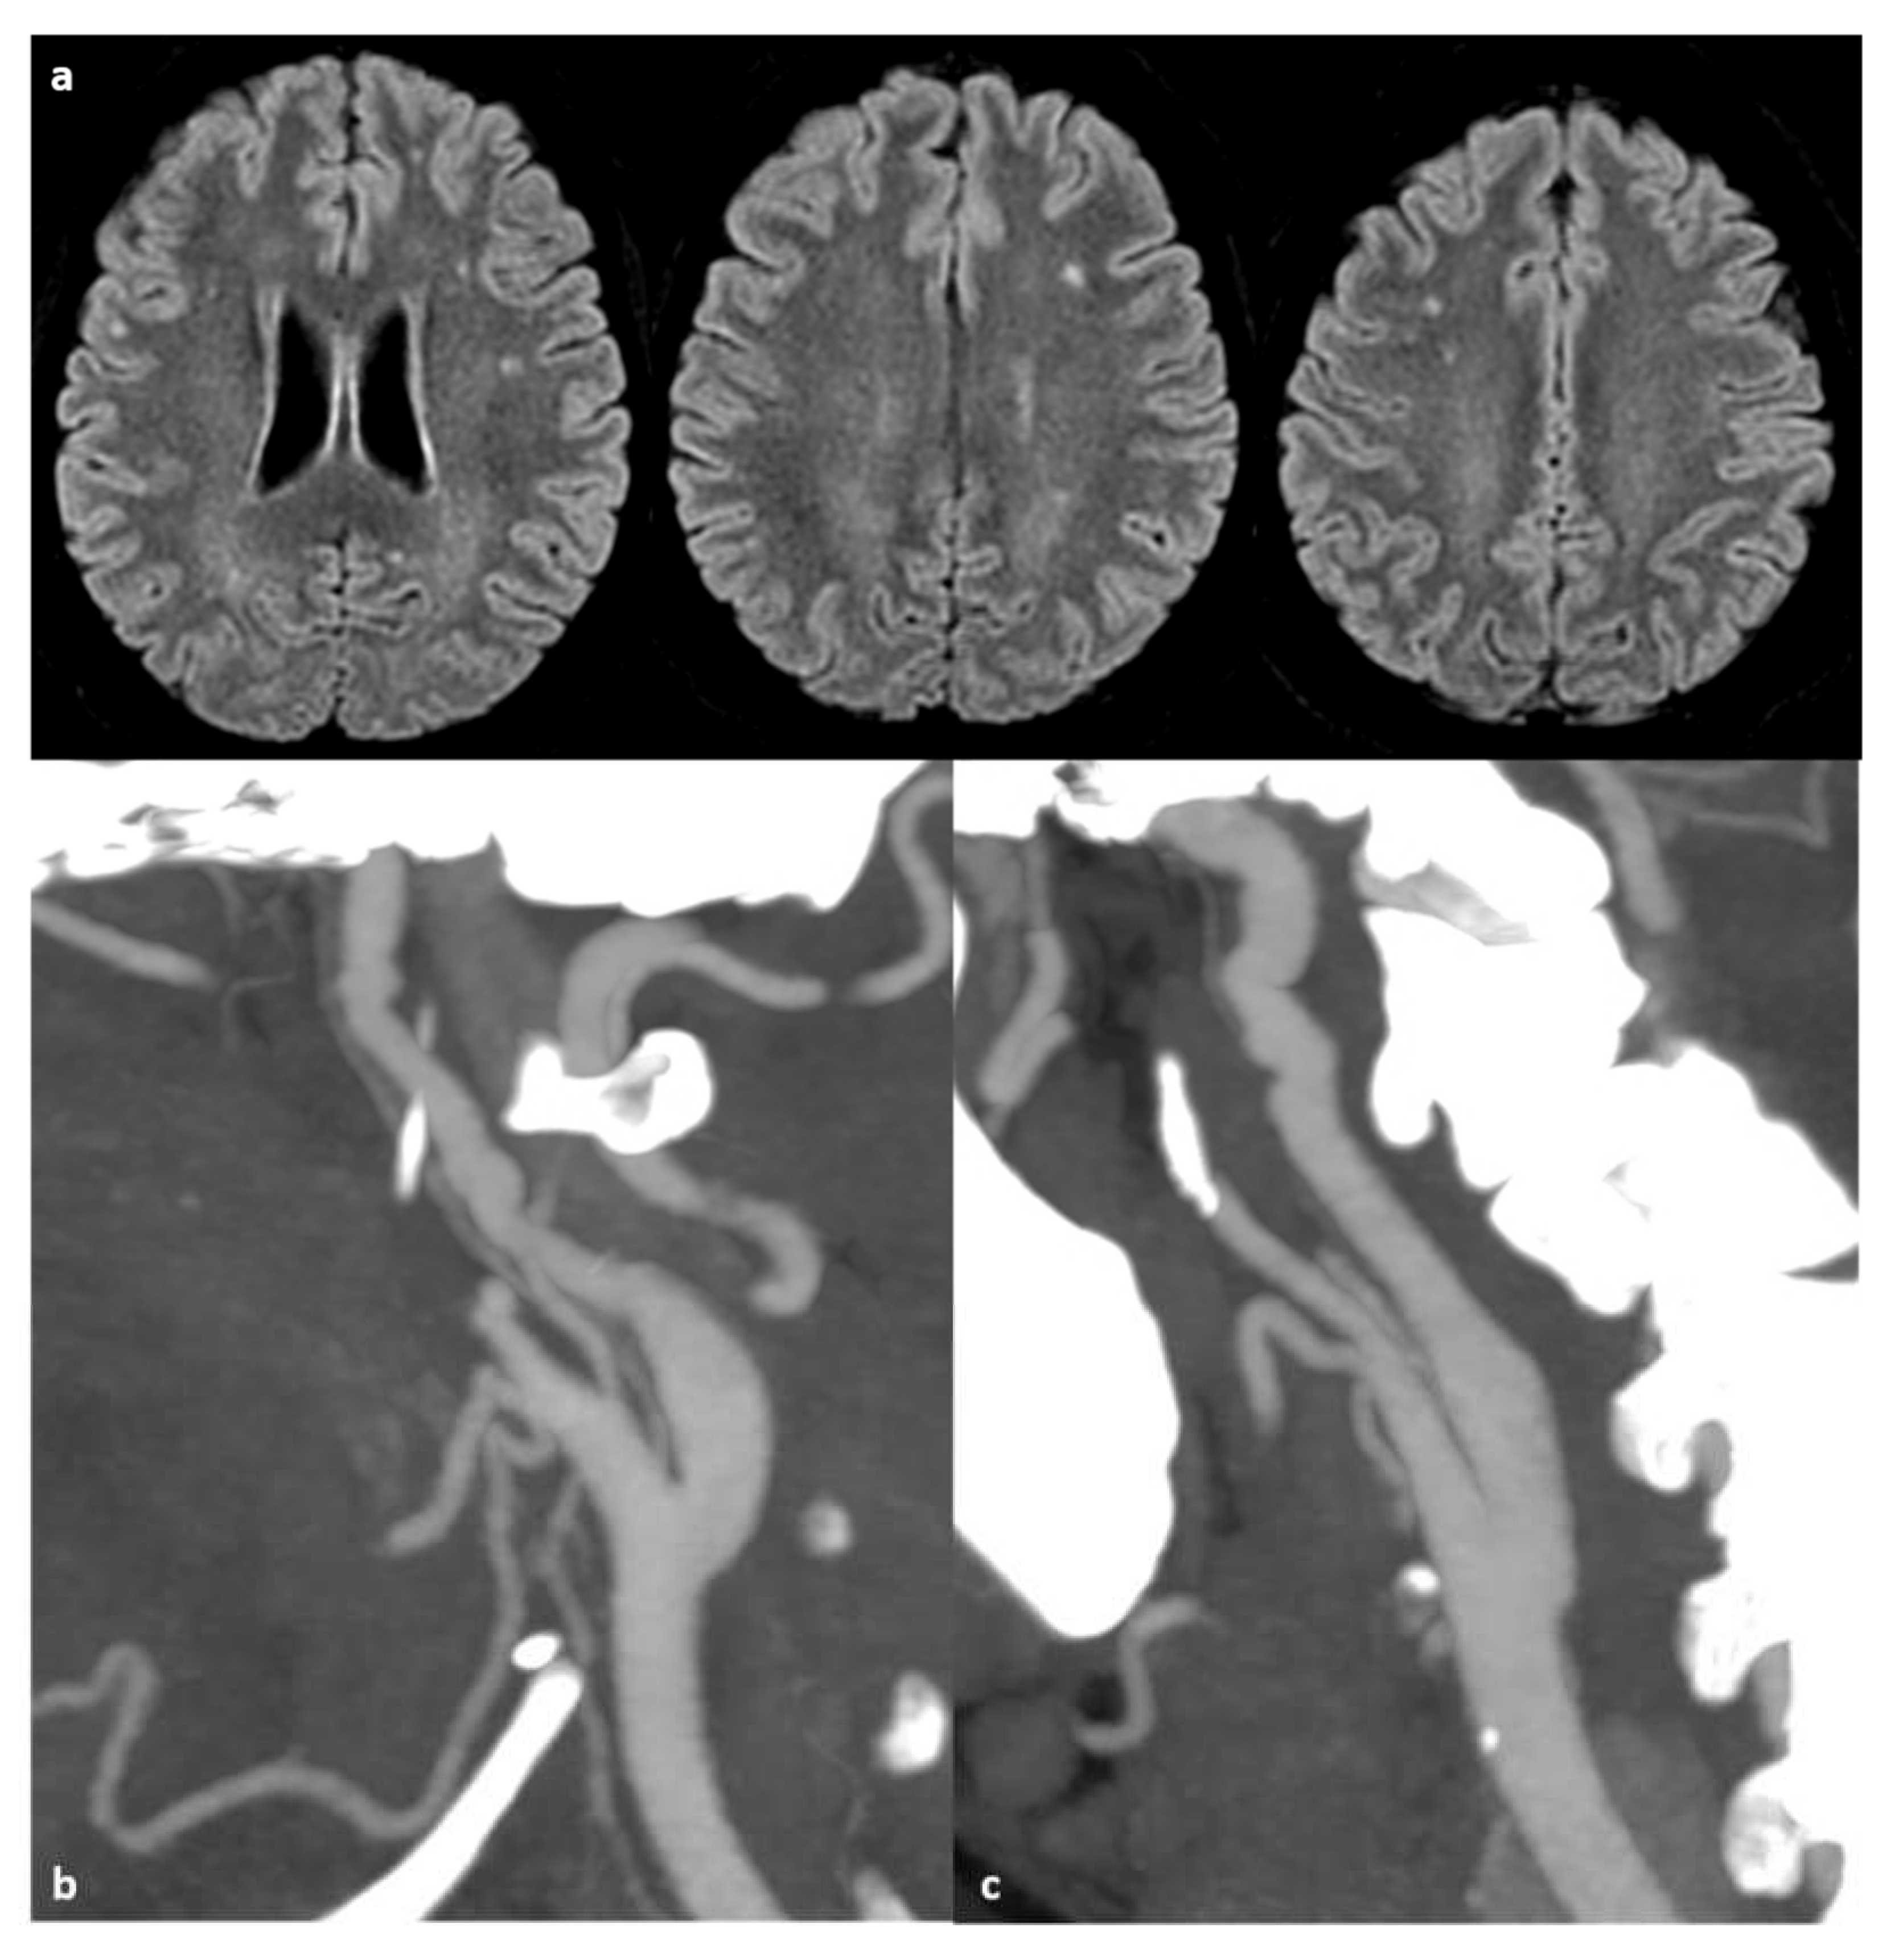

- Stotesbury H, Kawadler JM, Saunders DE, Kirkham FJ. MRI detection of brain abnormality in sickle cell disease. Expert Rev Hematol. 2021 May;14(5):473-491. [CrossRef]

- Helton KJ, Adams RJ, Kesler KL, et al. Magnetic resonance imaging/angiography and transcranial Doppler velocities in sickle cell anemia: results from the SWiTCH trial. Blood. 2014;124:891–898.

- Guilliams KP, Fields ME, Ragan DK, et al. Large-vessel vasculopathy in children with sickle cell disease: a magnetic resonance imaging study of infarct topography and focal atrophy. Pediatric Neurology. 2017;69:49–57.